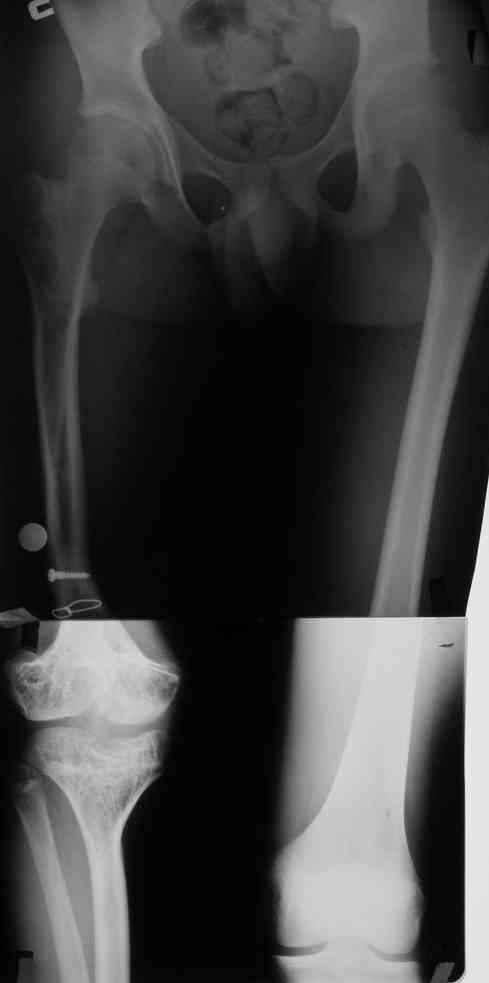

Re: Фиброзная дисплазия бедра, укорочение 12 см.

Спасибо за ответы. Это рентгенограммы пациента до и после последнего удлинения бедра